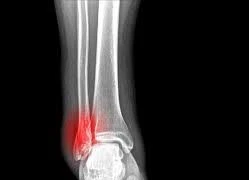

p lá khi gẫy xương là việc làm nguy hiểm, có thể khiến vết thương viêm nhiễm lan rộng hơn hoặc từ không viêm nhiễm trở nên viêm nhiễm, nếu không được điều trị kịp thời có thể dẫn đến nhiễm trùng huyết, gây ra viêm mủ màng tim, áp-xe phổi, viêm mủ màng phổi, viêm xương tủy xương, thậm chí…tử vong.